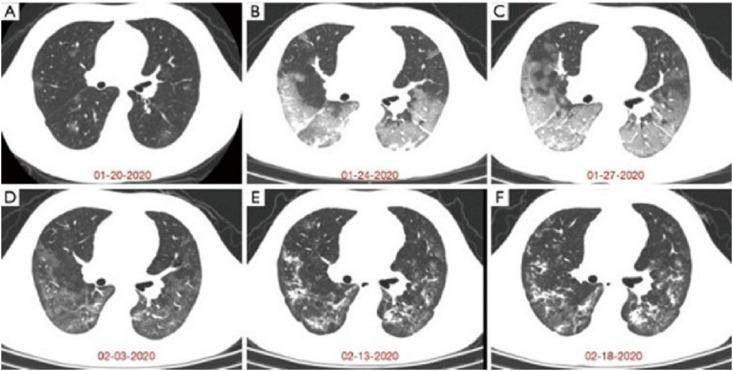

The ongoing pandemic of coronavirus disease 2019 (COVID-19) has been a great burden for the healthcare system in many countries because of its high transmissibility, severity, and fatality. Chest radiography and computed tomography (CT) play a vital role in the diagnosis, detection of complications, and prognostication of COVID-19. Additionally, magnetic resonance imaging (MRI), especially multi-nuclei MRI, is another important imaging technique for disease diagnosis because of its good soft tissue contrast and the ability to conduct structural and functional imaging, which has also been used to evaluate COVID-19-related organ injuries in previous studies. Herein, we briefly reviewed the recent research on multi-nuclei MRI for evaluating injuries caused by COVID-19 and the clinical H MRI techniques and their applications for assessing injuries in lungs, brain, and heart. Moreover, the emerging hyperpolarized Xe gas MRI and its applications in the evaluation of pulmonary structures and functional abnormalities caused by COVID-19 were also reviewed.

2019年冠状病毒病(COVID-19)的持续大流行给许多国家的医疗系统带来了巨大负担,因为它具有高传播性、严重性和致死性。胸部X线摄影和计算机断层扫描(CT)在COVID-19的诊断、并发症检测和预后评估中起着至关重要的作用。此外,磁共振成像(MRI),尤其是多核MRI,因其良好的软组织对比度以及进行结构和功能成像的能力,是疾病诊断的另一项重要成像技术,在先前的研究中也已用于评估与COVID-19相关的器官损伤。在此,我们简要回顾了多核MRI用于评估COVID-19所致损伤的最新研究以及临床MRI技术及其在评估肺、脑和心脏损伤中的应用。此外,还综述了新兴的超极化氙气MRI及其在评估COVID-19引起的肺部结构和功能异常中的应用。